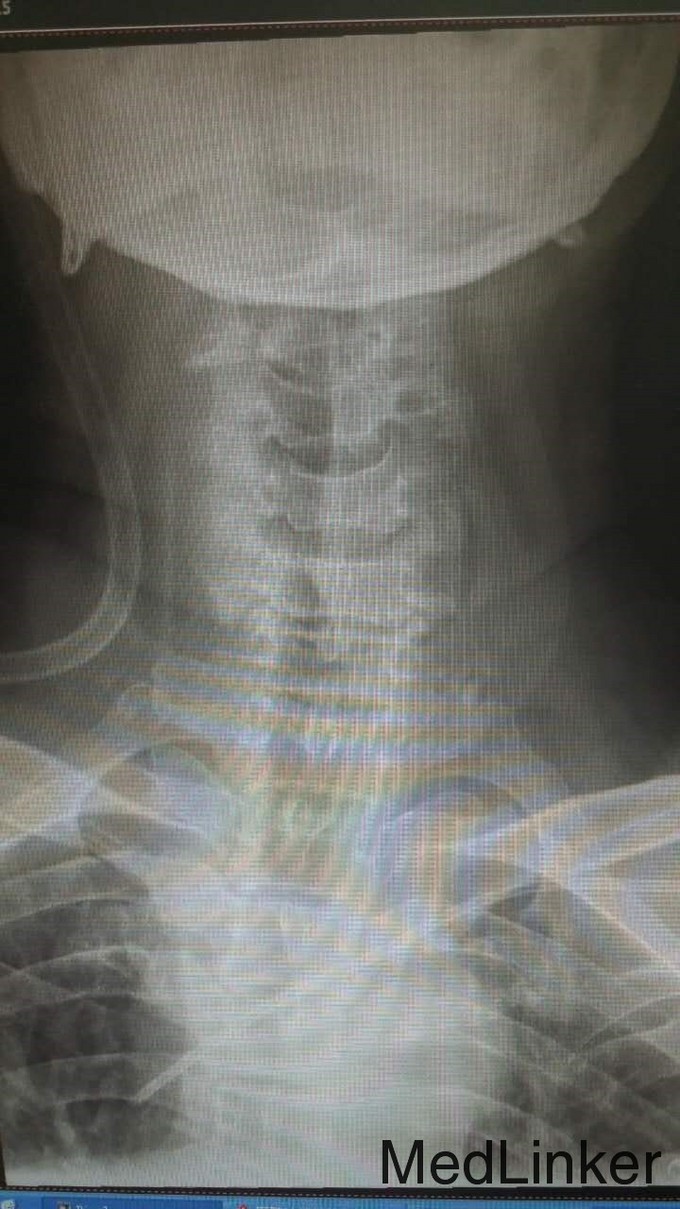

查体:T4平面以下痛觉消失,四肢肌力0级。双侧病理征阳性。 辅检:全身CT示:C4左侧椎扳、侧块、C5-6左侧横突多发骨折,C5椎体压缩骨折,C4椎体滑脱,颅内未见明显血肿,胸腹盆末见明显外伤行病变。头颅MRI示:C3-6水平颈髓出血伴水肿。

诊断:1.C3-6水平颈髓损伤出血伴水肿,2.C4左侧椎扳、侧块、C5-6左侧横突多发骨折,3.C5椎体压缩骨折,4.C4椎体滑脱(Ⅰ度) 治疗:伤后5天,予行C3-6椎板切除、椎管减压,侧块固定融合术